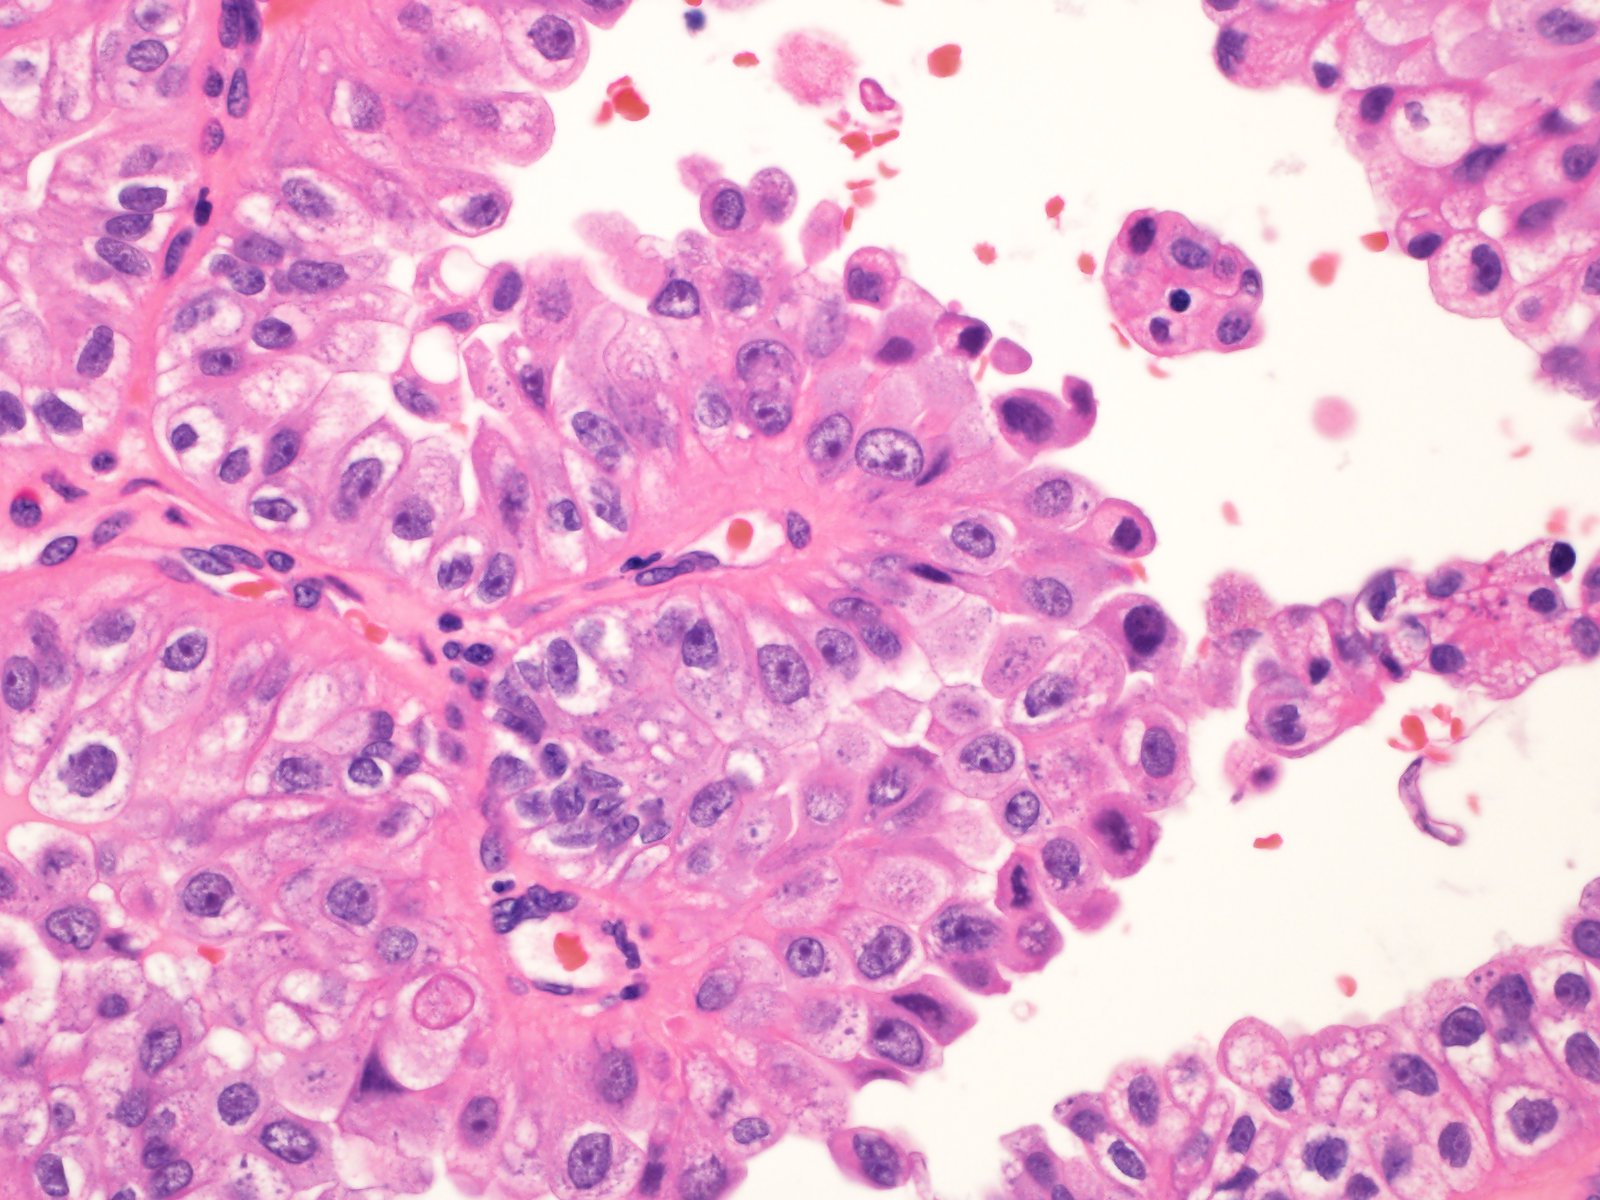

Renal tumor grading

Case ID: 839